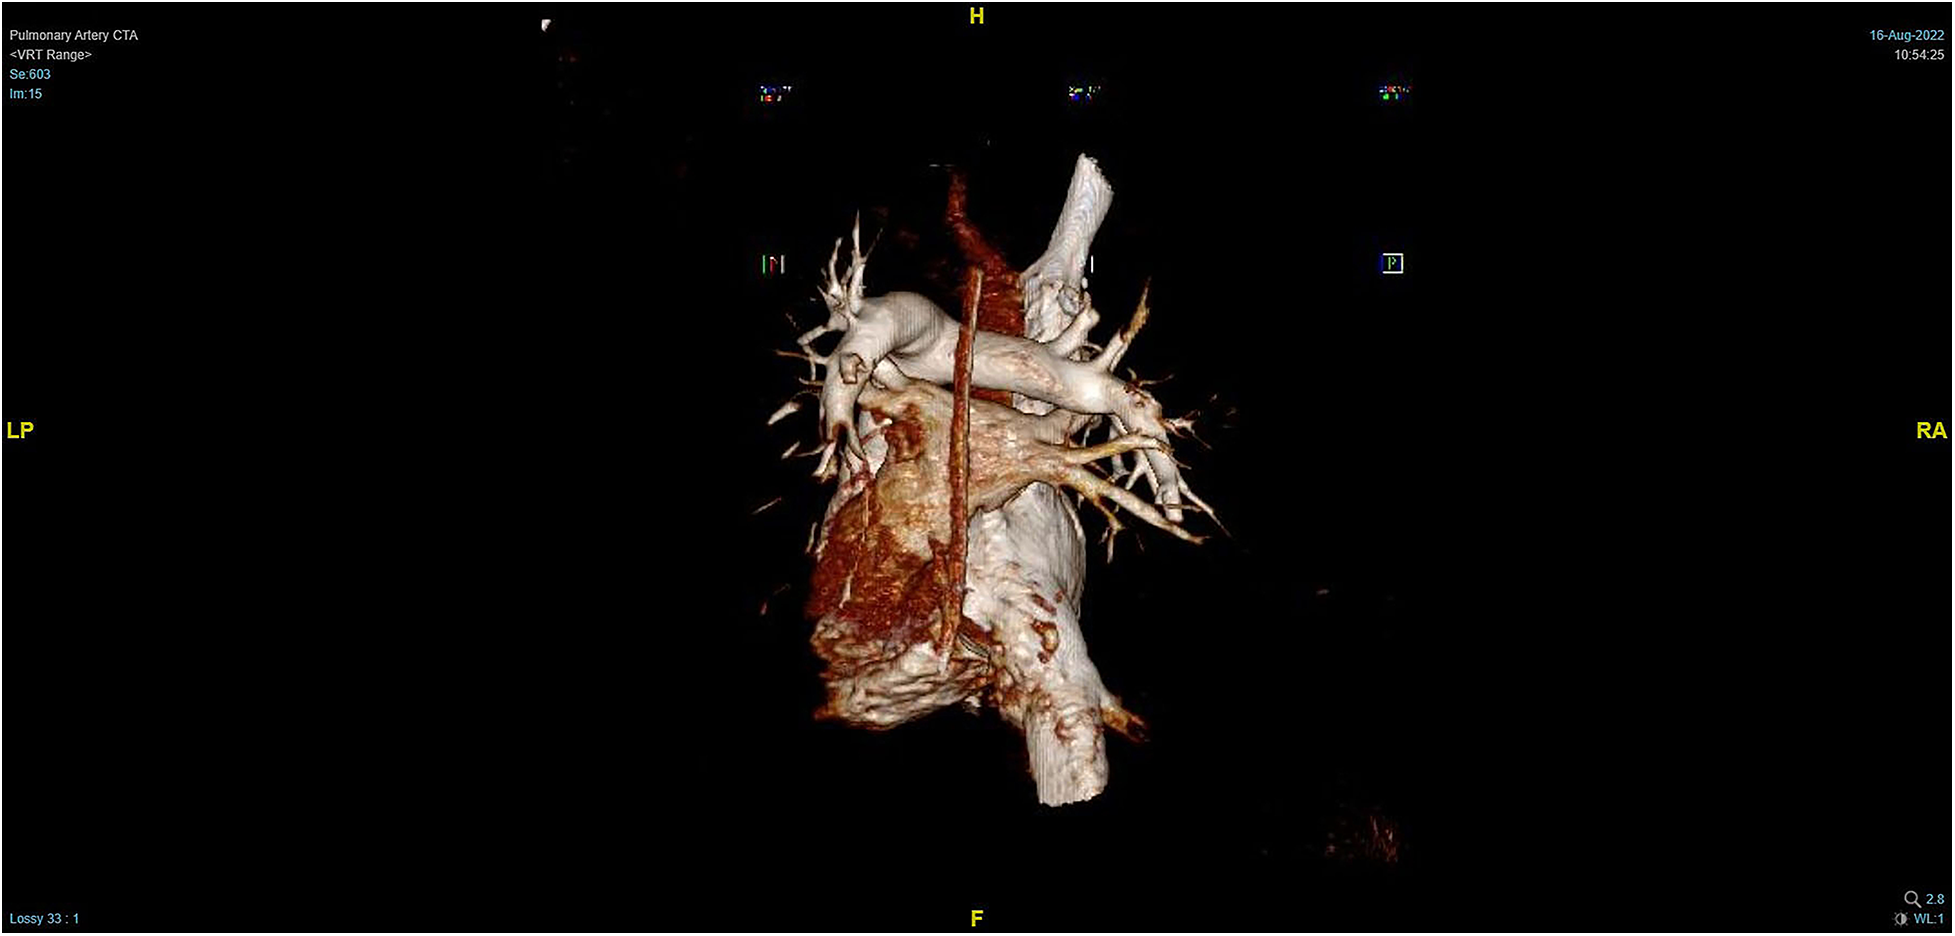

Figure 5

Massive pulmonary artery embolism.

During the procedure to surgically resect the right renal malignancy, the patient experienced decreased blood pressure, low-tidal carbon dioxide and high partial pressure of carbon dioxide in blood gas. After identifying a pulmonary embolism, the hepatobiliary surgeon performed a successful inferior vena cava embolectomy. The hemodynamics was still unstable after the surgery, with high pressure in the pulmonary artery, and the transesophageal ultrasound imaging revealed right ventricular dilation and strain, as shown in Figure 3. The ECMO team determined the indications for VA-ECMO assistance. Then, the right femoral artery was punctured immediately by inserting a 19 F cannula and the femoral vein was punctured by inserting a 21 F cannula. VA-ECMO was successfully established, thereafter, the respiratory status stabilized, and the patient was referred to the Department of Critical Care Medicine. The postoperative pulmonary artery computed tomography angiography (CTA) revealed strip-shaped filled defects in multiple branch arteries of the upper, middle, and lower lobes of the right lung, and the lower lobe and lingular segment of upper lobe of the left lung, and multiple pulmonary artery embolisms in both lungs (Figures 4, 5). Given the extensive embolization of the tumor in this patient, severe pulmonary hypertension may have developed earlier. Therefore, after comprehensive consideration, stronger drugs such as milrinone, ambrisentan, and treprostinil were given to reduce pulmonary artery pressure, along with VA-ECMO support.